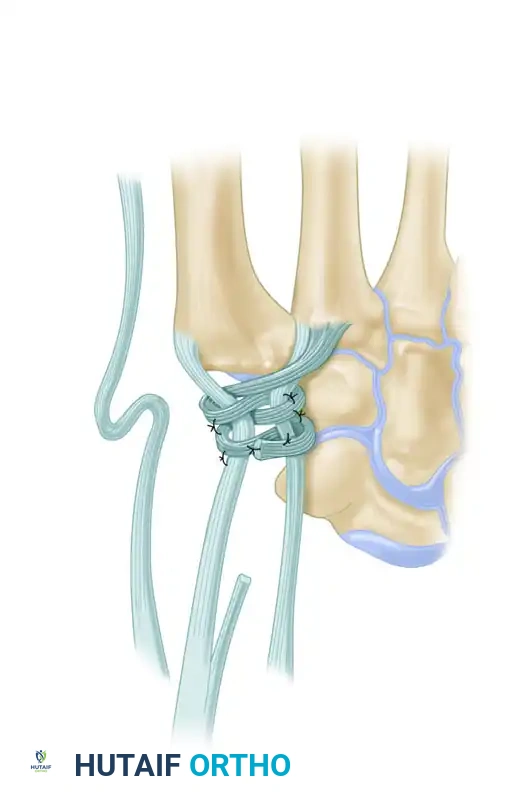

Figure B: FCR tendon passed through the bone tunnel while the index and thumb metacarpal bases are approximated.

Intraoperative view demonstrating the suspension of the first metacarpal.

- Intermetacarpal Securing: Pass the FCR tendon between the thumb and index metacarpal bases and secure it to itself with the same nonabsorbable suture.

*Figure C: FCR tendon passed between